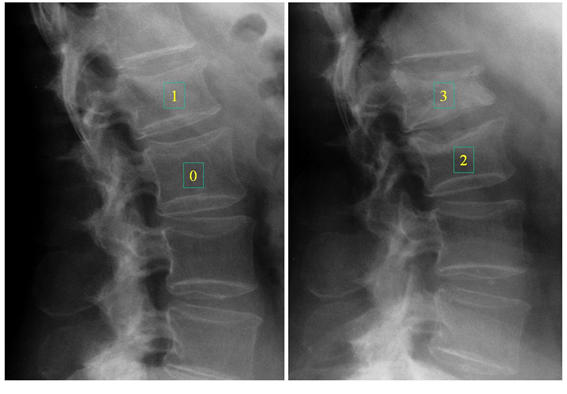

Due to the etiological complexity of back pain, it is common that an Osteoporotic fracture is not suspected and that it is often interpreted as muscle pain, such as a contracture. Another finding is the loss of height, which is usually gradual. The most frequent location of VF is in the middle region of the dorsal column T7 and T8 as well as in the dorsolumbar junction T12 - L1 as we see in Figure 2, Figure 3 and Figure 9 Many of these symptoms can become disabling. physically and psychologically due to its persistence, producing depression, social isolation and interpersonal relationship problems as well as difficulty falling asleep due to pain and depression, leading in severe cases to the loss of social identity.

Figure 2 Vertebral fractures at level T8 and T11, numbers 1 and 3 on the radiographs show the Genant classification: 1 mild and 3 severe.

Figure 3 Lumbar vertebral fractures, the number 0 is normal, 1,2 and 3 show different VF (Genant Classification).

Grade 1 has a previous height reduction of 20 to 25% and an area reduction of 10 to 20%, moderate (grade 2) of 25 to 40% and area reduction of 20 to 40%, severe (grade 2). grade 3) of more than 40% at any height and area. This method has been evaluated and tested in different epidemiological studies and clinical studies with drugs. In Figure 3 the number 0 is normal, 1 corresponds to grade 1, mild; the number 2 to a grade 2 and 3 to a severe Genant grade 3, is calculated from the “vertebral deformity index” P: length of the posterior wall, A: length of the anterior wall, therefore: PA/P x 100 = % that P is less than A. With this method, the IFC (spinal fracture index) can also be calculated by adding all the grades assigned to the vertebrae and dividing by the number of vertebrae.